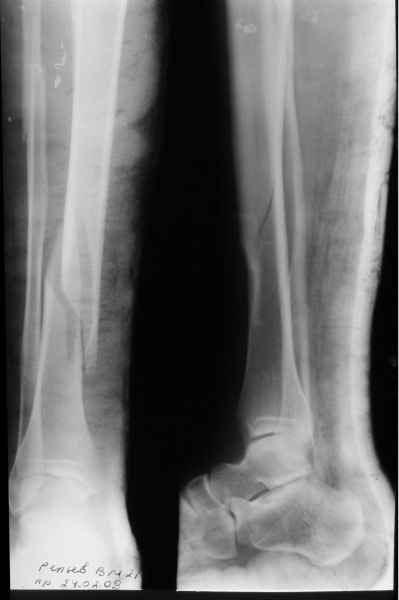

Из тона Вашего сообщения следует, что необходимо согласиться с этим,поскольку это и есть ИСТИНА. И вообще сторонники БИОСа предлагают не лезть со своими аппаратами внешней фиксации к диафизарным переломам вообще. Кстати,новым аппаратом я пролечил, ни много ни мало, уже 103 пациента. 4 дня назад я снял аппарат с 22-летнего пациента с простым косопоперечным переломом костей голени. 45 дней фиксации, из которых 30 он ходил без дополнительных средств опоры с полной нагрузкой. 3 перевязки за весь период лечения. Около 3 недель адаптационной нагрузки и его можно выписать к труду. Сегодня снял аппарат пациентке 36 лет. Фиксация 49 дней. История та же. Через два дня собираюсь снять аппарат 28-летней пациентке, 45 дней фиксации. На прошедшей неделе прооперировал 4 пациентов с переломами костей голени, во всех случаях идеальная репозиция и есть уверенность, что никто из них не донесет аппарат до 50 дней. Вопрос: чем лучше БИОС? Или я что-то недопонимаю?